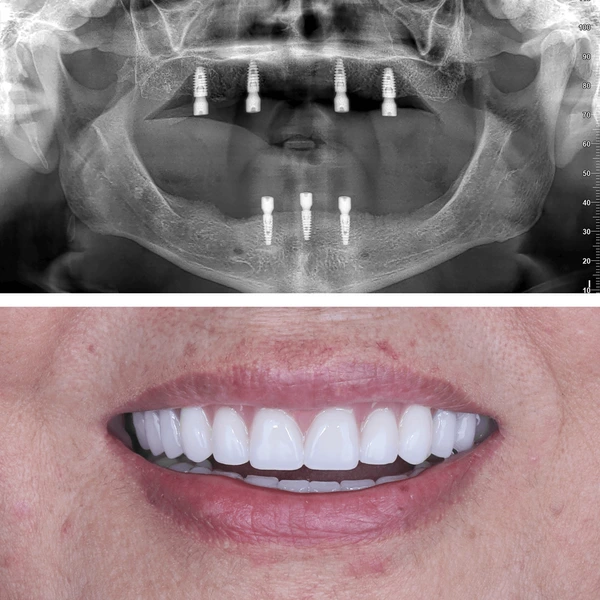

Eso es exactamente lo que determinamos en la evaluación. Revisamos tu hueso y encías con radiografía panorámica. Y dato importante: muchas personas que creen que no pueden, sí pueden. Solo hay que evaluarlo bien.

Usamos marcas con reconocimiento internacional y décadas de respaldo clínico. Un implante es para toda la vida, por eso elegimos solo lo mejor disponible en el mercado — y te explicamos por qué en tu evaluación.